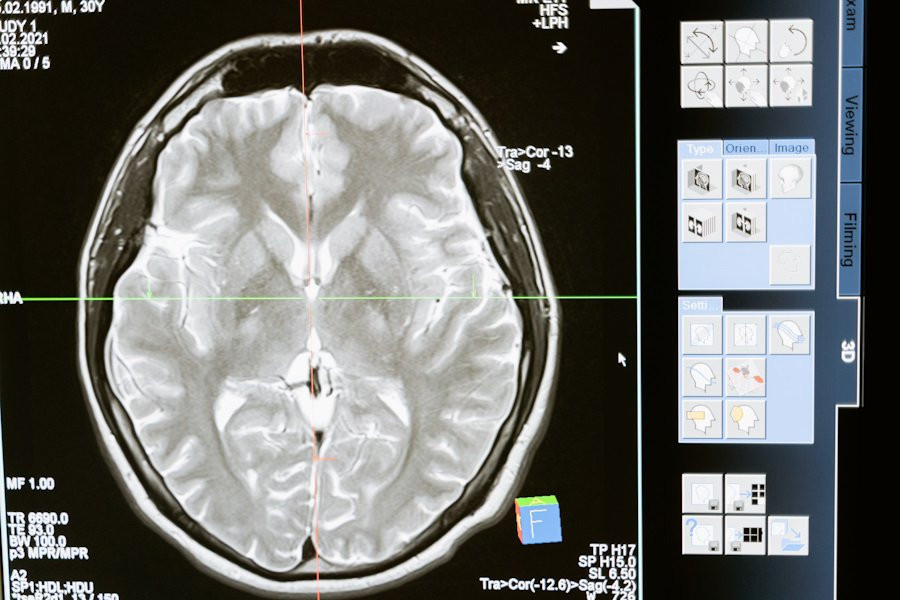

Группа ученых из Института цитологии и генетики СО РАН и ТПУ совершила прорыв в области медицинской науки, обнаружив способность наночастиц проникать в клетки нейронов обонятельных луковиц носа, сообщается на РИА Новости.

Исследователи утверждают, что эти частицы могут быть управляемы с помощью переменного магнитного поля, что открывает двери для направленной доставки в специфические участки головного мозга и воздействия на его функции.

Согласно обнародованным данным, эта методика предоставляет новые перспективы для лечения нейродегенеративных заболеваний. Предыдущие попытки управления нейронами с применением наночастиц осуществлялись извне, однако в данном исследовании удалось продемонстрировать способность даже простых нанороботов проникать внутрь нейронов, что открывает новые горизонты для медицинской науки.

Один из ученых, старший научный сотрудник ИЦиГ Александр Ромащенко, выразил удивление и радость по поводу этого прорыва: «Впервые в мире нам удалось продемонстрировать, что даже простейшие нанороботы способны проникнуть внутрь нейронов, и их передвижение по организму можно успешно контролировать, воздействуя на клетки изнутри».

Эти результаты исследования могут иметь значительное влияние на область медицины. Направленная доставка нанороботов в глубокие участки головного мозга открывает возможности для новых методов лечения нейродегенеративных заболеваний. Также данная технология может использоваться для доставки лекарственных препаратов, включая те, которые направлены на лечение опухолей головного мозга.